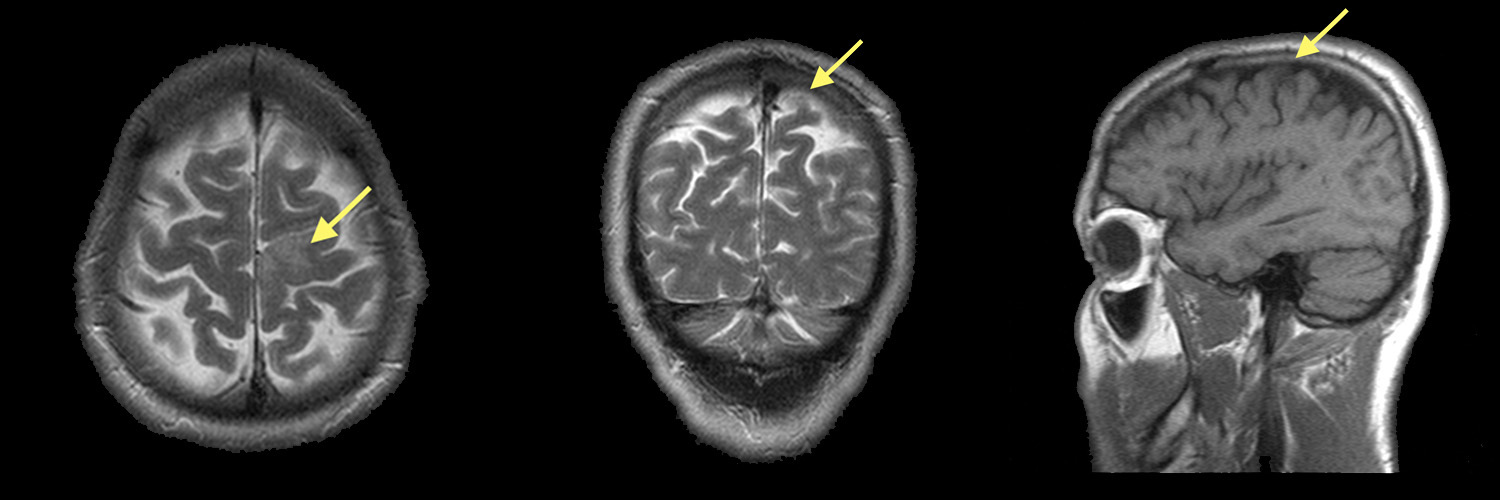

Хроническая ишемия головного мозга и лейкоареоз: симптомы и лечение